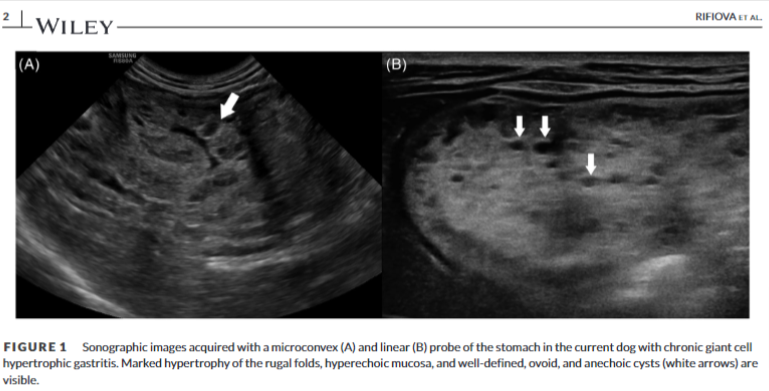

| 메네트리에 유사 질환(Ménétrier-like disease, MLD)은 개에서 매우 드물게 발생하는 위 질환으로, 사람의 메네트리에 질환과 유사한 특징을 보입니다. 이 질환은 위 점막의 비대와 낭포성 변화를 특징으로 하며, 주로 노령견에서 발생합니다. 주요 증상으로는 식욕 부진, 체중 감소, 구토 등이 있으며, 심한 경우 저알부민혈증이나 단백질 소실성 장병증이 나타날 수도 있습니다. 진단은 주로 영상 검사와 조직 검사를 통해 이루어집니다. 복부 초음파에서는 위벽이 두꺼워지고, 점막이 비대해져 주름이 위 내강으로 돌출되어 있는 모습을 관찰할 수 있습니다. 또한, CT 검사에서는 뇌회 모양의 위 점막 주름이 특징적으로 나타납니다. 조직 검사를 통해 foveolar hyperplasia, lamina propria의 샘 비대, 낭포성 확장 등을 확인하여 확진할 수 있습니다. 치료는 아직까지 명확하게 확립된 방법은 없지만, 증상 완화를 위해 약물 치료나 수술적 치료를 시도할 수 있습니다. MLD는 예후가 좋지 않은 질환으로 알려져 있으며, 적절한 치료에도 불구하고 사망에 이를 수 있습니다. 따라서 조기에 진단하여 적극적으로 치료하는 것이 중요합니다. |

초음파 특성은 위와 같다. 보통 위벽의 비후가 일반적인 원인에 일어나는경우 muscularis가 비후되는 경우가 많은데 이 증례는 뚜렷한 점막의 비후 양상이 보이며, cyst가 보이는게 특징적이다.